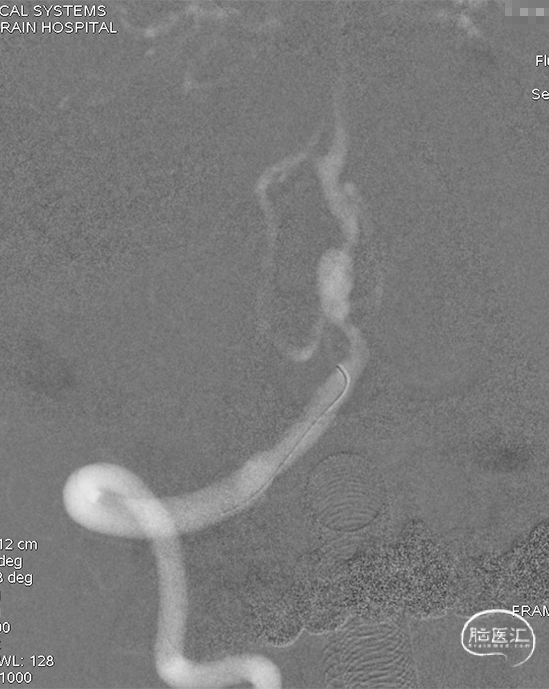

DSA示双侧椎动脉V4段狭窄,右侧为著且合并梭形动脉瘤。

术前DSA。